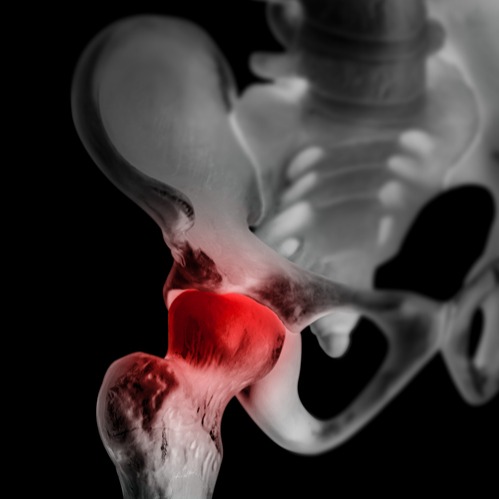

L'osteonecrosi, conosciuta anche come necrosi avascolare o necrosi ischemica dell'osso, è una condizione caratterizzata dalla necrosi (ossia dalla morte) del tessuto osseo, a causa di una ridotta o interrotta irrorazione sanguigna all'osso interessato. Questo può portare alla rottura strutturale dell'osso e al collasso delle articolazioni nelle aree colpite.

Le ossa maggiormente interessate da questa condizione patologica sono il femore e l'omero.

In base alle zone interessate dalla condizione, si possono osservare sintomi specifici; nell’osteonecrosi dell’anca, per esempio, il dolore può svilupparsi tra l’inguine e la coscia, limitando la capacità di deambulare